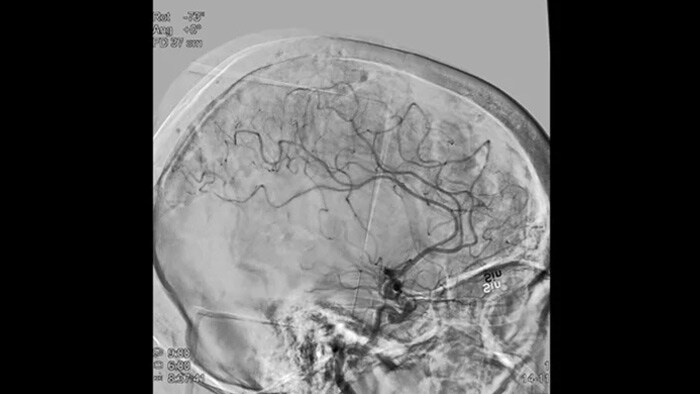

Scharfe Bilder dank 2D DSA mit ClarityIQ

2D DSA mit ClarityIQ

Die automatische Bewegungskompensation von ClarityIQ ermöglicht auch während Echtzeit-DSA scharfe Bilder der Gefäße und unterstützt so die sichere Entscheidungsfindung während Schlaganfallbehandlungen.

DSA Visualisierung

Hochwertige DSA-Visualisierungen ermöglichen es Ihnen, zu beurteilen, ob das Gerinnsel vollständig entfernt wurde und ob sich Teile davon distal in das Gehirn verteilt haben. Sie können die Wiederherstellung des Blutflusses zur Penumbra verifizieren und eine Überprüfung auf periprozedurale Blutungen vornehmen.